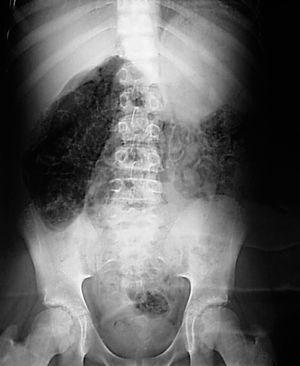

Se realizó radiografía simple de abdomen, objetivando patrón radiolucente en el espesor de la pared intestinal con imágenes microvesiculares quísticas difusas, sin presencia de aire ectópico (figs. 1 y 2). Se confirmó el diagnóstico mediante realización de TC abdominal, realizando coprocultivos y determinación de rotavirus en heces, así como antigenemia a citomegalovirus, con resultados negativos. El estudio se completó con biopsia intestinal que resultó normal.

Figura 1. Radiografía simple de abdomen en la que se observa una imagen compatible con neumatosis intestinal.